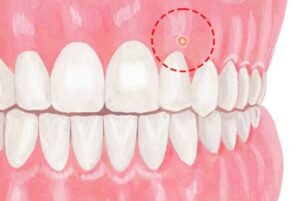

「歯ぐきに白いできものができている」「ニキビみたいにぷくっと腫れている」「つぶれたり、またできたりを繰り返す」――このような症状がある場合、それはフィスティル(瘻孔:ろうこう)かもしれません。

フィスティルとは、歯ぐきにできる小さなできもののような出口のことです。見た目は白っぽいニキビや吹き出物のように見えることがあり、「歯ぐきにニキビができた」と感じる方も少なくありません。

これは単なるできものではなく、歯の根の先などにたまった膿(うみ)が外へ出るための通り道です。体が炎症を外へ逃がそうとして作る排出口ともいえます。

押すと膿が出たり、一度治ったように見えてもまた同じ場所にできたりすることもあります。